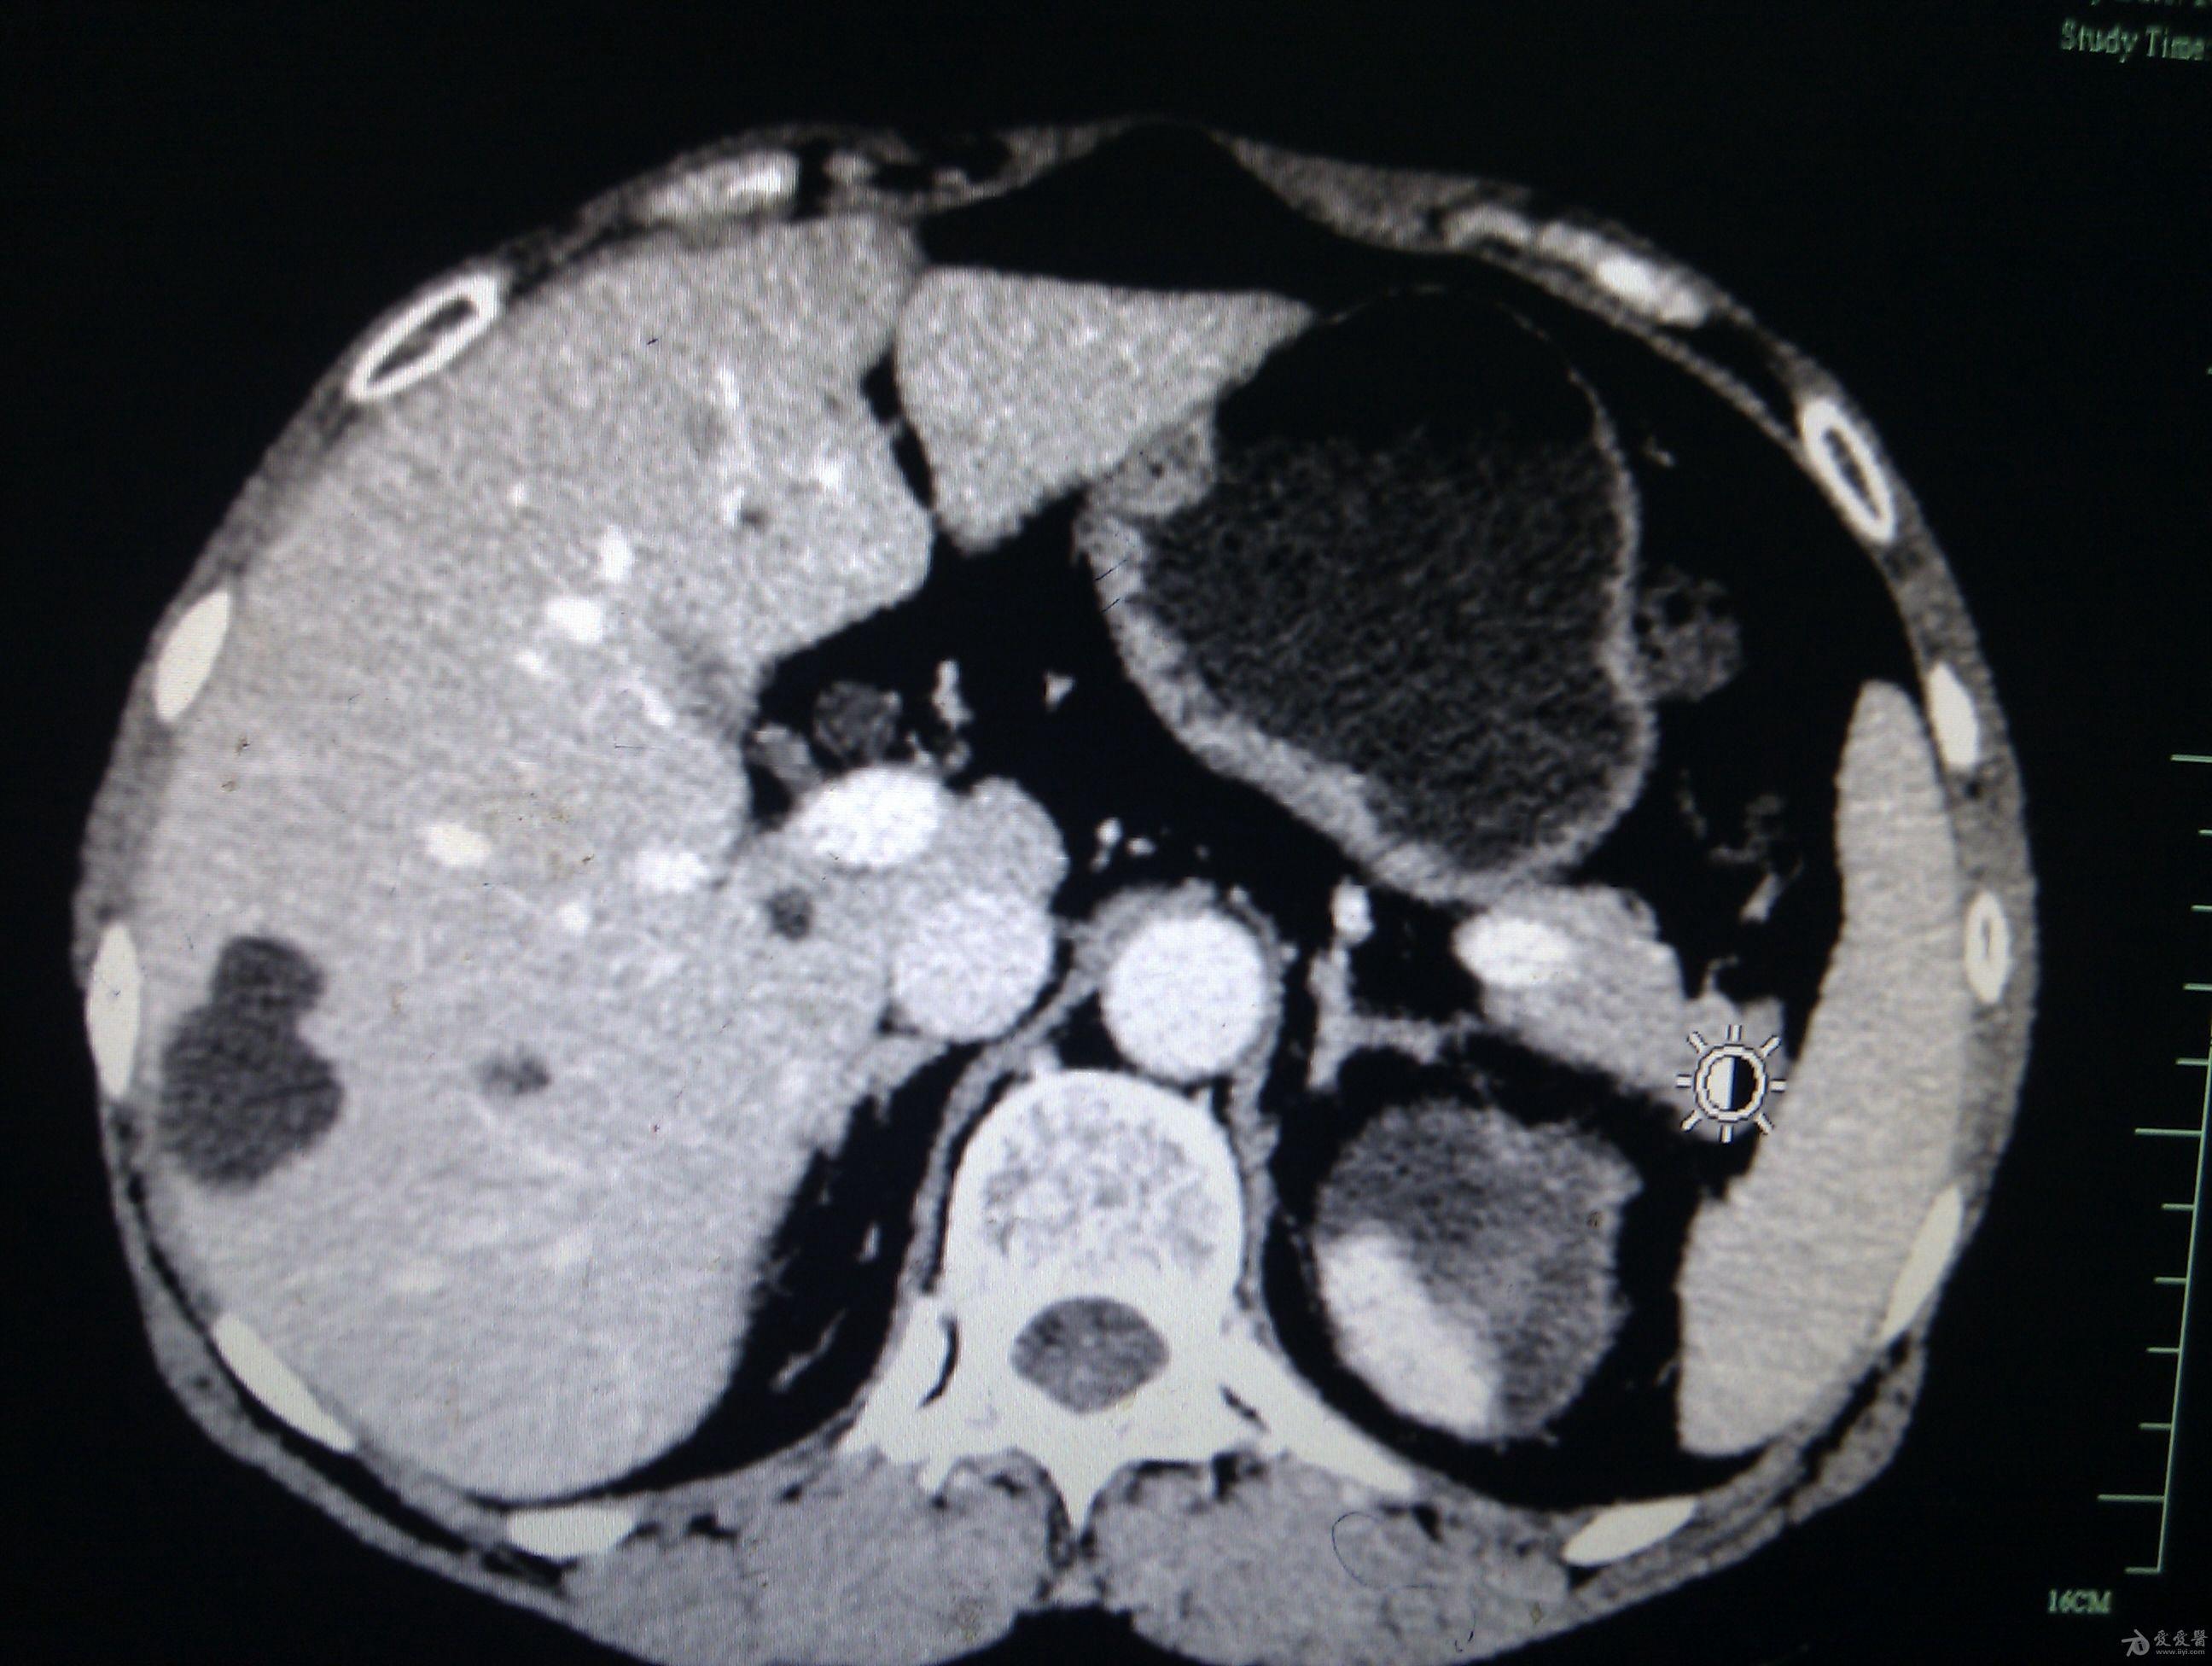

左肾包膜下血肿